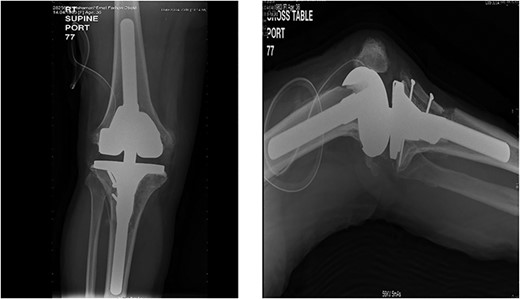

The patient lost some of her range of motion (ROM) in the post-operative period even with extensive physiotherapy. On her 4-month follow up appointment; ROM was 10–80°, which she sustained afterward. Plain radiographs continued to show no new HO formation at 4 months (Fig. 5).

Knee X-rays at 4 months visit continued to show no new HO formation, and continuation of healing of the osteotomy.